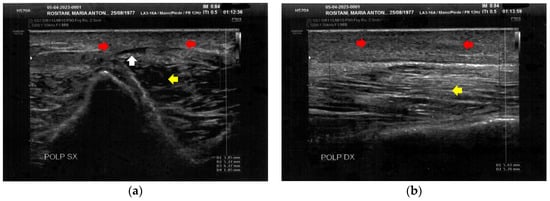

3.2. Imaging Evaluations After the Treatment